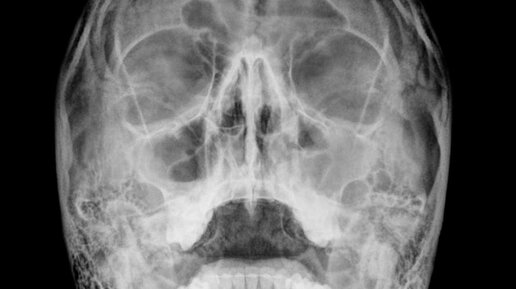

Чем отличается синусит от гайморита? Объясняем разницу между общим понятием и конкретным диагнозом. Синусит и гайморит: одно и то же или нет? Многие считают, что синусит и гайморит — это разные заболевания. На самом деле, это не так. Чтобы разобраться, нужно понять анатомию. У человека есть четыре пары околоносовых пазух: гайморовы (верхнечелюстные), лобные, решётчатые, клиновидные. Когда воспаляется любая из этих пазух, ставится диагноз «синусит» — это общее название воспаления околоносовых пазух...

Внутри костей лицевого черепа имеются полости. Эти полости связаны с полостью носа и называются придаточные пазухи носа или синусы. Воспаление одной или нескольких пазух называется синусит. В зависимости от того какая пазуха поражена меняется и уточняется диагноз. Например: Гайморит- воспаление верхнечелюстной пазухи. Фронтит- воспаление лобной пазухи Этмоидит - воспаление в решетчатой кости. Сфеноидит- воспаление клиновидной кости. То есть гайморит это частный случай синусита. Часто синусит является...